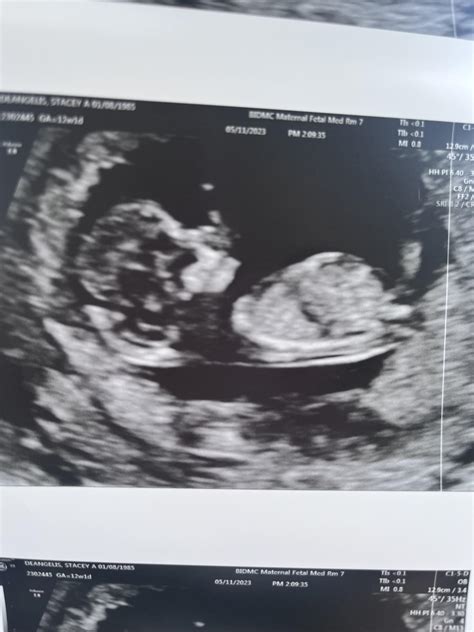

11 Week Ultrasound Pictures

Pregnancy is an exciting journey filled with milestones, and one of the most anticipated moments is the 11-week ultrasound. This scan provides valuable insights into the baby's development and offers parents their first detailed glimpse of their growing child. Understanding what to expect from 11 week ultrasound pictures can help alleviate anxiety and build excitement for this significant event.

At 11 weeks, the baby has undergone significant development. Some of the key milestones include:

• The baby's head makes up nearly half of the entire length, and the body is starting to straighten out.

• The tail, which is a normal part of early development, is still visible but will disappear soon.

• The baby's heart beats strongly, and the heartbeat can often be heard during the ultrasound.

• The baby's limbs are more defined, with tiny hands and feet becoming more visible.

• The baby's organs, including the liver, kidneys, and intestines, are developing rapidly.

Interpreting 11 Week Ultrasound Pictures

11 week ultrasound pictures can reveal a wealth of information about the baby's development. Here are some key features to look for:

• Crown-Rump Length (CRL): This measurement is taken from the top of the baby's head to the bottom of the buttocks. It helps determine the baby's gestational age and overall growth.

• Heartbeat: The baby's heart should be beating strongly and steadily. The heartbeat is a crucial indicator of the baby's health.